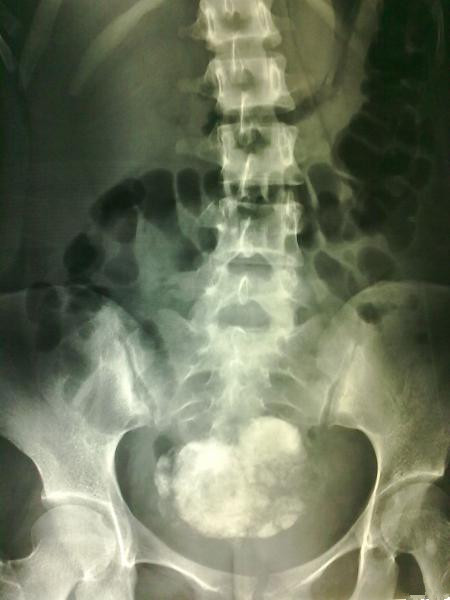

查体:生命体征平稳,心肺无特殊,下腹部压痛轻,中下腹部反跳痛明显。未扪及包块。 辅助检查:血常规正常,凝血正常。彩超:右下腹部短杆样肠管改变。子宫及附件无异常。肝胆脾无异常。腹部立卧位:不完全性肠梗阻,盆腔占位。

入院后保守治疗,患者症状无明显缓解,与患者及家属沟通,行剖腹探查术,术中发现该肿物发自右侧卵巢,呈带蒂装,肿物大小约12cm*8cm*5cm,边界清楚,质地硬,可见骨骼样组织。术中考虑是畸胎瘤。肿物送病理检查。

术后病理结果回报:右侧卵巢纤维瘤。 讨论:卵巢纤维瘤是卵巢性索间质肿瘤中常见的良性肿瘤。临床上可出现盆腔包块、伴胸腹腔积液、腹痛、月经障碍等症状,部分患者无症状,仅在体检或手术时偶然被发现。在治疗上以手术治疗为主。发病原因尚不明确。